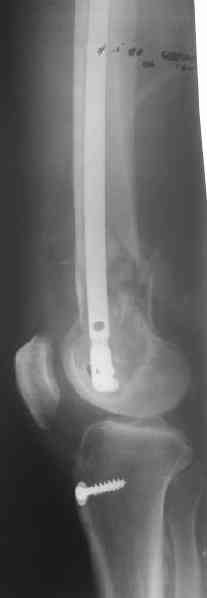

It appears to me as if someone has already tried to "Mold" or contour this plate - there seems to be an extra angle in it. This plate should not be contoured, since the shape of it (the 95 degree angle) is what allows it to be used , when inserted correctly, to re-establish the relationship between the joint and shaft axes.

I think the primary problem is "simply" a translational one and not a major angular deformity. I wonder if the shortening is more related to contracture than loss of bone. I would obtain long alignment films (hip- knee-ankle), and perhaps a scanogram, or at least separate bilateral femur films, to try and sort these issues out.

I think I would favor treatment to healing in this position, with aggressive PT and then re-evaluate the extent of disability. Nutritional and medical optimization and a bone stimulator may be worth considering. The presence of a cerclage wire in an area of comminution is often forensic evidence of bone murder. I am not optimistic that a retrograde nail would lead to secure healing and would worry about taking it all apart at this stage.

Jeff Anglen